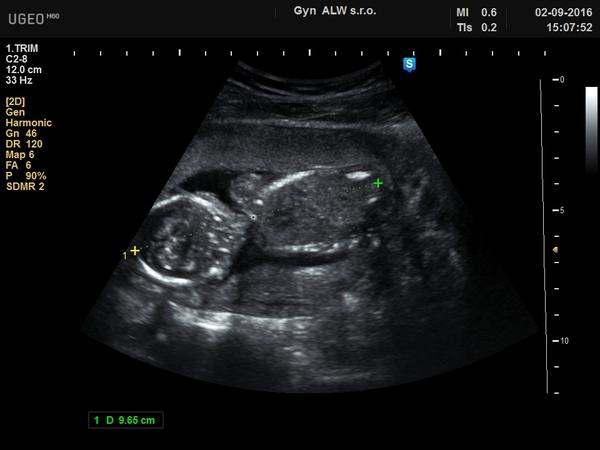

@ddaniela123 Já bych se asi taky přikláněla k holčičce. Ukážu ti ultrazvuk mého nejstaršího a mé nejmladší, je to z 19.tt, takže podobně jako ty, tak třeba ti to pomůže 😀 😉

@zoditka Tak u Tebe ta holcibja byla jasna🙂)). Me tam mate u te moji fotky ten vyrustek, co vypada jako pindik🙂))doma mam 16 leteho syna, tak bych si prala holcinku. Jinak moc dekuji

@alexis01 pindik jak vysitej 😉